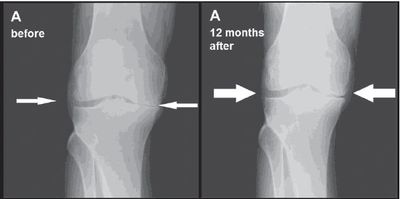

In the phase I safety trial, a single injection of adipose tissue derived stem cells into the knee patients was safe and well tolerated.

The stem cell treatment also showed durable and clinically meaningful pain relief in patients with knee osteoarthritis.

Examination of knee joint structure by MRI showed a statistically significant improvement in lateral tibial cartilage volume for patients treated with the stem cells. This result compared to a worsening in volume in placebo patients.